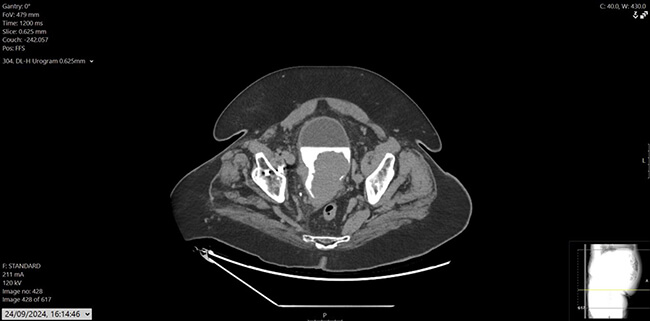

His prostate specific antigen (PSA) had decreased from 43.6ug/L in December 2022 to 0.02ug/L. He also had a history of hypertension, osteoarthritis, and hypercholesterolemia, with mixed lower urinary tract symptoms (LUTS), managed on tamsulosin. Flexible cystoscopy revealed a large mass on the left lateral bladder wall, with CT imaging confirming a bladder mass and thickening at the bladder dome. Mild pericaecal fat stranding and lymphadenopathy were also noted (Figure 1, 2 and 3). Preoperative blood work showed stable parameters.

Figure 2: CT urogram, axial.